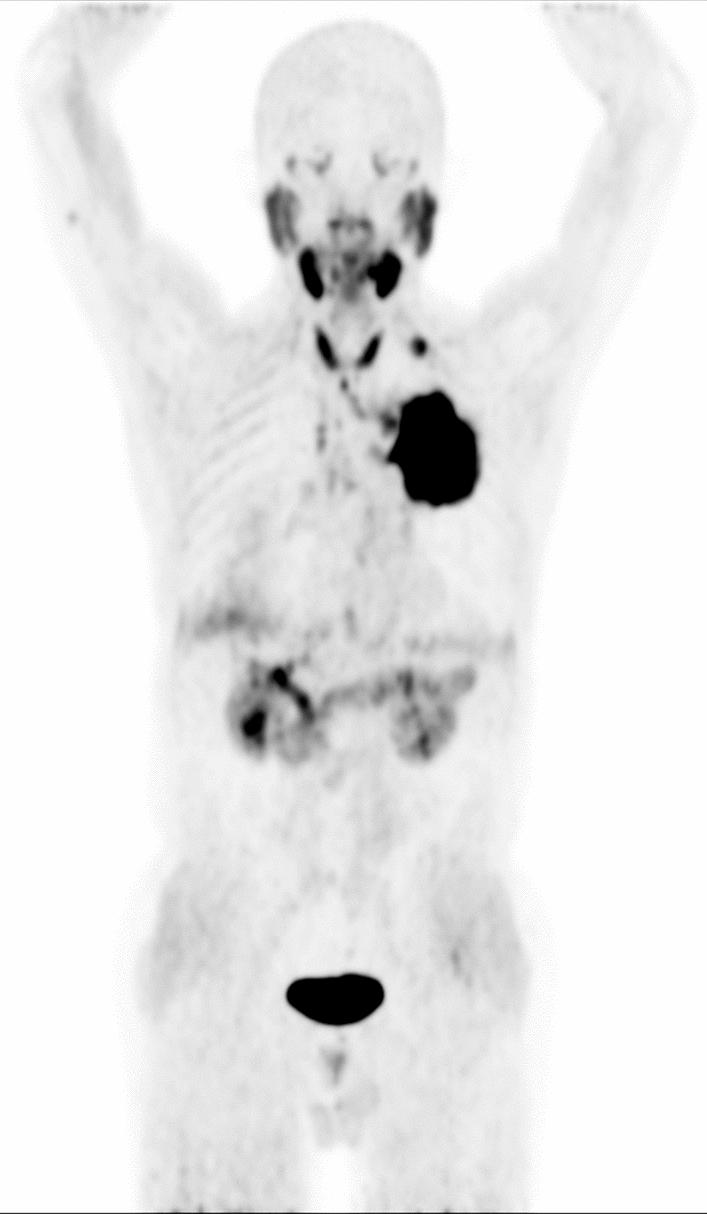

Many patients undergoing [F] AlF-NOTA-FAPI-04 (F-FAPI) PET/CT demonstrated diffuse thyroid uptake. These findings created challenges for accurate interpretation due to the limited understanding of physiological and non-oncologic causes of diffuse F-FAPI uptake in the thyroid. This retrospective study examined patients who underwent F-FAPI PET/CT imaging with diffuse thyroid uptake. It quantitatively assessed normal thyroid uptake, compared F-FAPI uptake between normal and diseased thyroids, and explored potential associations with diffuse thyroid uptake. The study may improve the accuracy of F-FAPI PET/CT interpretation for thyroid and facilitate appropriate management of diffuse thyroid uptake on F-FAPI PET/CT.

A total of 38 patients were included in this study based on the inclusion criteria. The mean SUVmax, SUVmean, and TBR of normal thyroid were 7.09 ± 3.83, 4.24 ± 2.25 and 3.93 ± 1.73, respectively. Quantitative analysis revealed no significant asymmetry in F-FAPI uptake between the right and left thyroid lobes (SUVmax: right 6.69 ± 2.96 vs. left 6.54 ± 3.28, p = 0.84; SUVmean: right 4.19 ± 1.73 vs. left 4.18 ± 1.97, p = 0.98), consistent with the diffuse uptake pattern observed. There was no significant correlation between Hashimoto thyroiditis, serum TSH levels, and the degree of diffuse thyroid uptake (all p > 0.05 for SUVmax, SUVmean, and TBR). Furthermore, no association was observed between sex, age, immunotherapy, and diffuse thyroid uptake (p > 0.05).

CONCLUSIONS

Diffuse uptake of F-FAPI in the thyroid may not significantly relate to Hashimoto thyroiditis or abnormal serum TSH levels. Lesions on F-FAPI PET/CT scans might be hard to detect due to the moderate uptake in normal thyroid tissue.